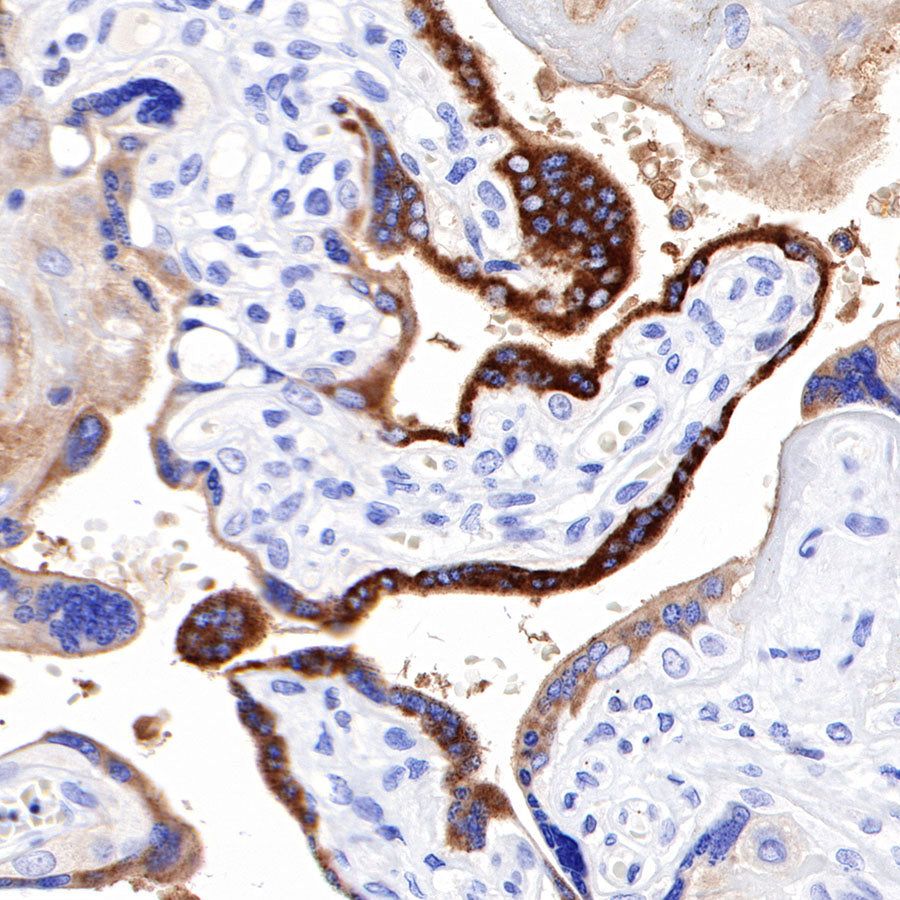

Immunohistochemistry

IHC shows positive staining in paraffin-embedded human placenta. Anti-PAPP-A antibody was used at 1/1000 dilution, followed by a HRP Polymer for Mouse & Rabbit IgG (ready to use). Counterstained with hematoxylin. Heat mediated antigen retrieval with Tris/EDTA buffer pH9.0 was performed before commencing with IHC staining protocol.